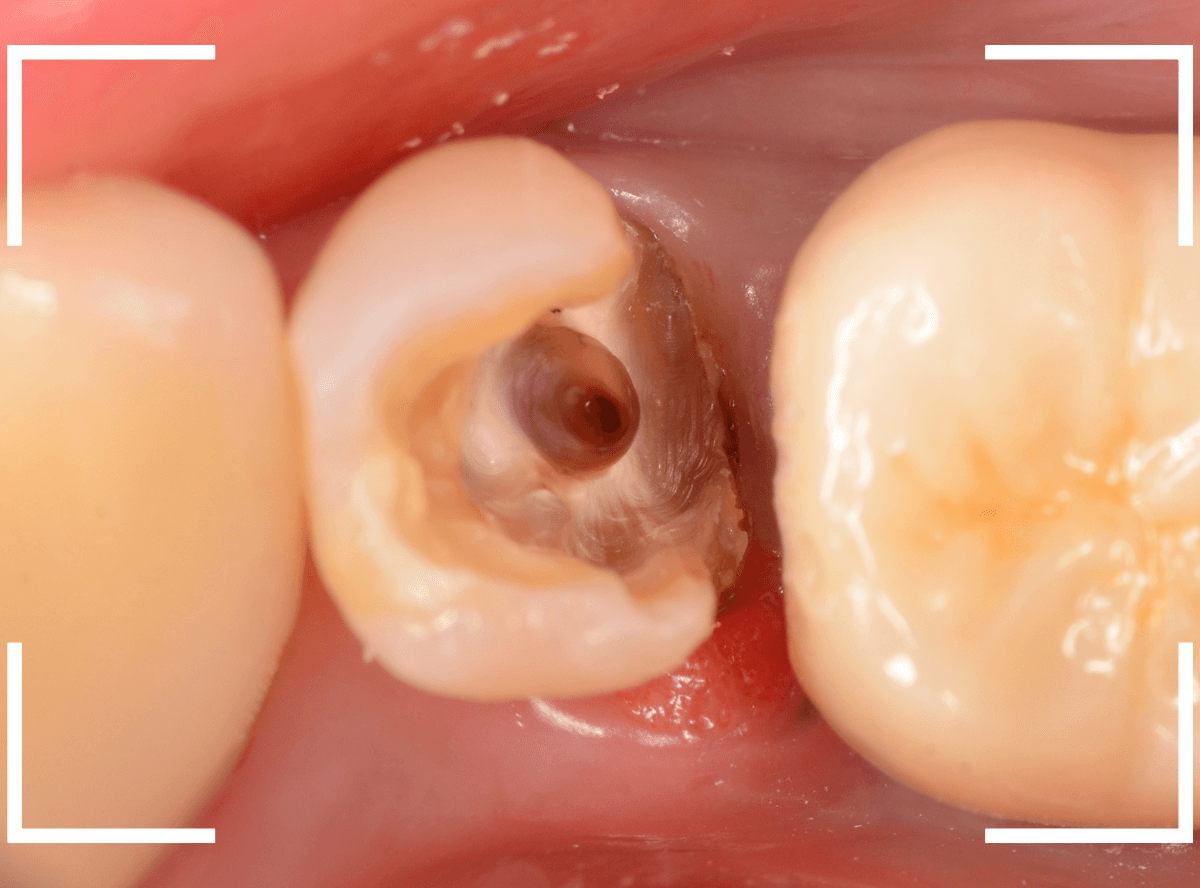

さし歯を作る前にまず、歯の補強(コア)処置をします。

セラミック・インレーを除去し、歯の内部もある程度削ります。

歯の内側をコアで補強後、さし歯で被せるために、歯全体を削ってトリミングし、型取りします。